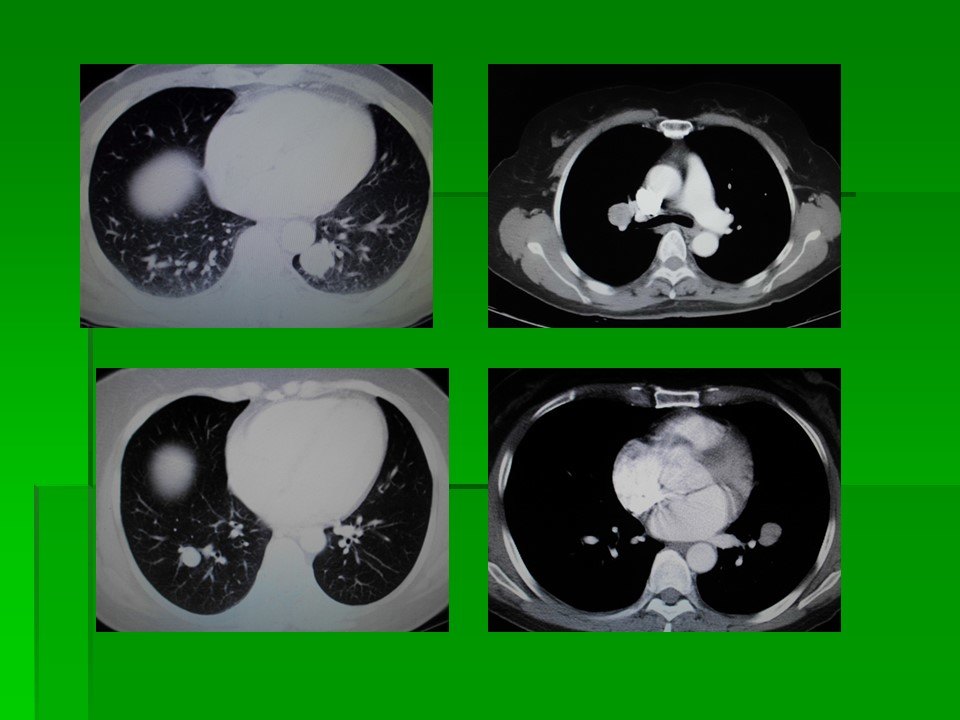

肺结节读片 13 生长极快的小细胞肺癌结节 复查

肺结核合并肺癌的ct表现及鉴别诊断 影像ppt